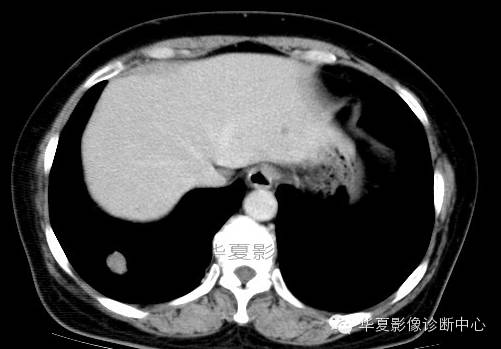

影像资料:

术中切除(右下)部分肺组织7x6x2cm,切面见一灰白色肿物,直径2cm,质较脆,与周围组织界限清,略呈分叶状,无包膜。

(右下肺)错构瘤(以软骨成份为主)

肺错构瘤多发生在胸膜下肺表浅部位,呈球形、椭圆形,有完整的包膜,质硬,易与周围肺组织分开。肺错构瘤的直径0.5~12cm,多数小于3cm。肿瘤剖面呈灰白色,质硬,有黏液和囊腔。主要成分有软骨、腺体、平滑肌、脂肪及纤维组织等。肿瘤可发生钙化,多位于中心,分布较均匀,此种钙化结构常像爆米花样或核桃肉样。